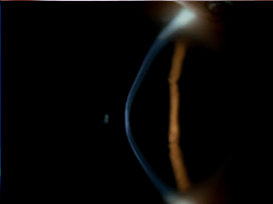

眼部侧面图(角膜中央向前凸出)

经检查,阿雨右眼角膜中央呈典型“圆锥形”凸出,伴随角膜混浊,角膜OCT检查显示中央厚度仅约332微米,远低于正常角膜厚度,已处于圆锥角膜晚期。

那么,圆锥角膜究竟如何“偷走”视力?申海静主任通俗比喻:正常角膜像均匀的半球形透镜,能让光线精准聚焦在视网膜上;而圆锥角膜患者的角膜组织强度不足,在眼内压力作用下,中央或旁中央区域逐渐变薄外凸成圆锥状,如同凹凸不平、带划痕的相机镜头,光线无法正常聚焦,进而导致高度不规则散光和视力扭曲。